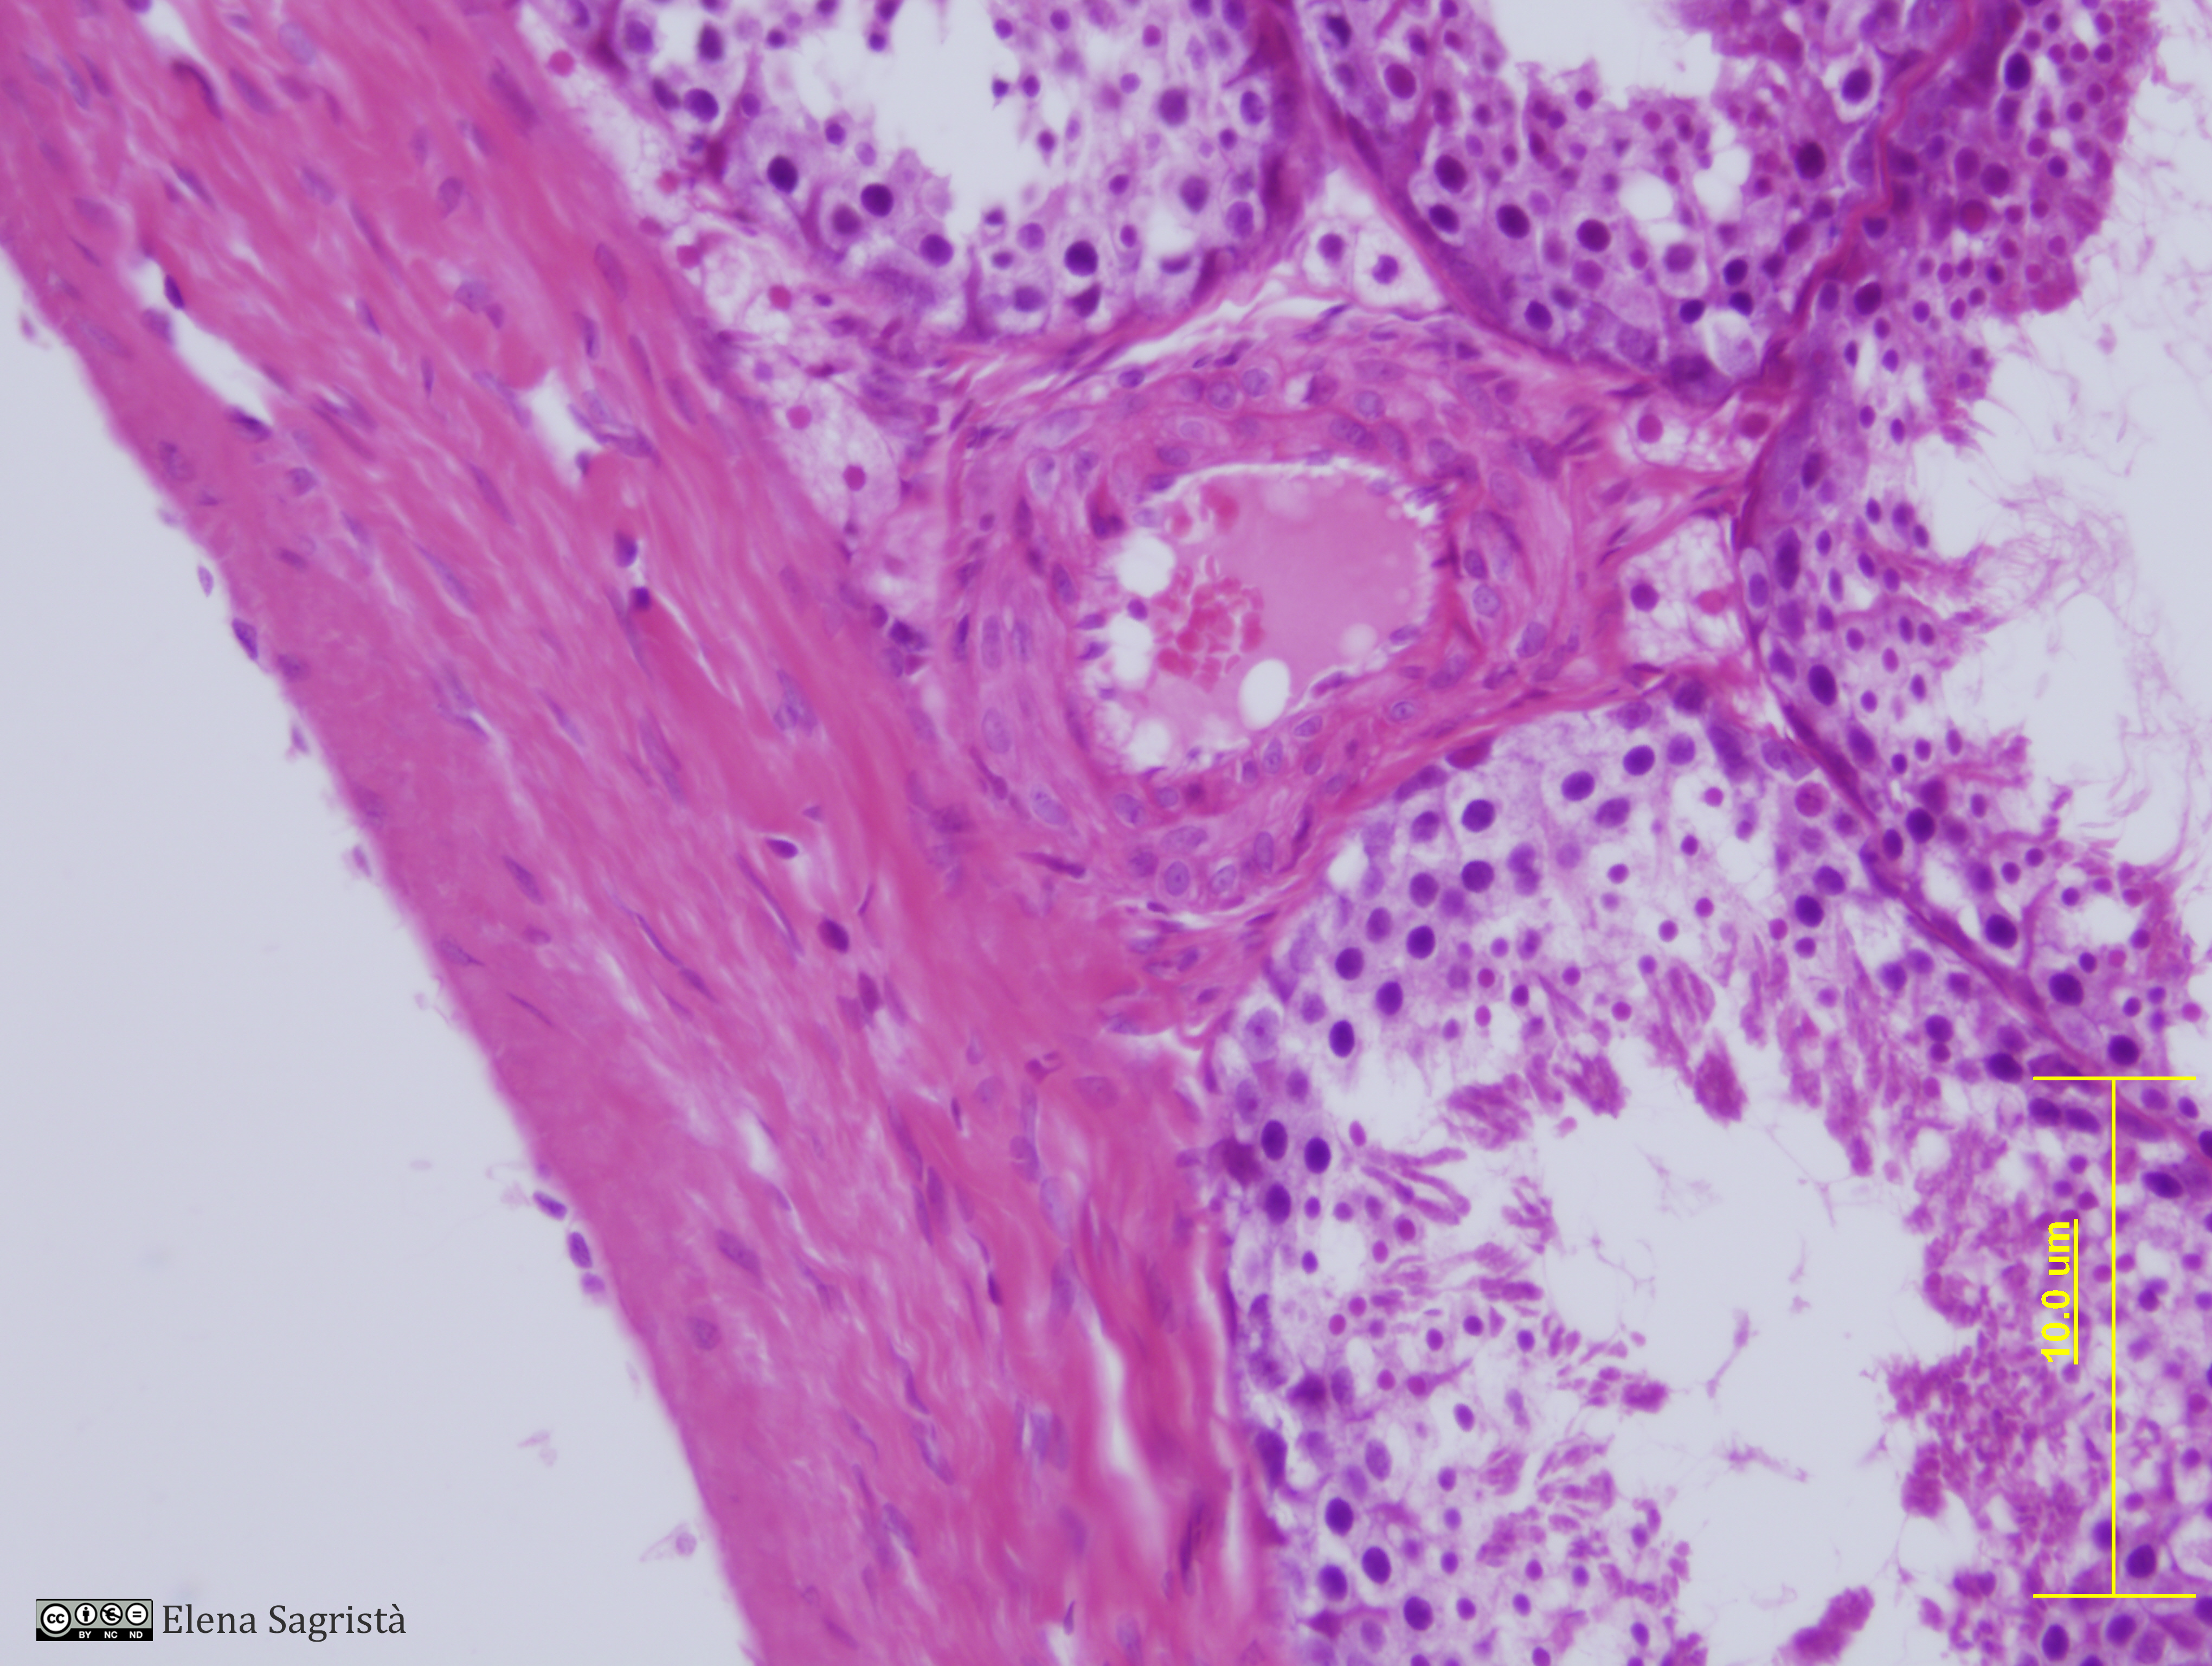

Histologia imatges: 22 Testicle

Imatges de preparacions histològiques de Testicle. Microscopia òptica.